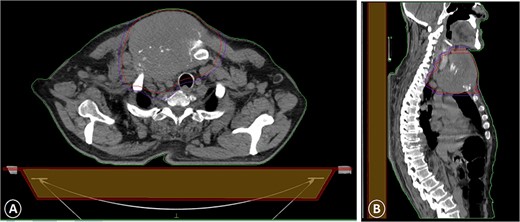

The patient was diagnosed with stage 3 colon cancer, and the standard of care to be given adjuvant chemotherapy was FOLFOX (leucovorin calcium, fluorouracil, and oxaliplatin) or XELOX (capecitabine ‘Xeloda’ and oxaliplatin). However, the patient has maintained on adjuvant therapy XELODA alone due to its poor performance status with comorbidities. During follow-up after the third cycle of adjuvant XELODA chemotherapy, the patient came with a rapidly enlarging, painful, hard mass on the upper part of his sternum over the last month (Fig. 2). A biopsy of the sternum confirmed metastatic adenocarcinoma consistent with the known primary colon cancer. A CT simulation was done and demonstrated a single destructive lesion in the sternum (Fig. 3). The patient received external beam radiotherapy (EBRT) to the sternum, consisting of 30 Gy delivered in 10 fractions, resulting in symptomatic improvement and a reduction in mass size post-treatment (Fig. 4). The patient was evaluated 3 months after finishing radiotherapy, with a good general condition and resolution of the sternal mass, and he is on a regular follow-up in the radiation oncology clinic.

Significant clinical resolution of the mass size post radiation therapy treatment.